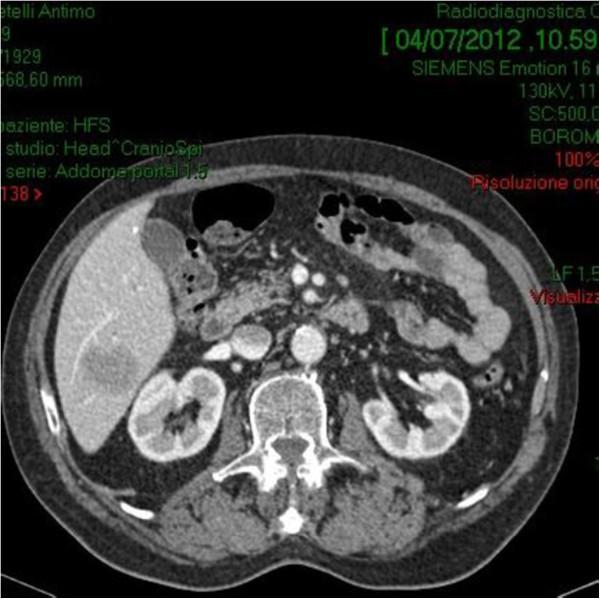

A 70-year-old male with a 6-mo history of vague abdominal pain, constipation and melena was referred to our hospital. Computed tomography scan of abdomen revealed the presence of a mass along the proximal ascending colon. Colonoscopy biopsy showed external compression of the cecum with two ulcerations of mucosa, but it was not consistent for a definitive diagnosis. Because the difficulties in the preoperative pathological diagnosis, the high risk of bowel obstruction and the correlated hemorrhagic risk, the patient underwent a right hemicolectomy associated with locoregional lymphadenectomy and liver resection.The surgically resected right colon and liver tumors were all immunohistochemically diagnosed as diffuse large B-cell lymphomas (DLBCL). The patient refused any other antineoplastic treatment; he is alive and free of disease at 3 years after initial diagnosis.

一名70岁男性,有6个月的腹部隐痛、便秘和黑便病史,转诊至我院。腹部计算机断层扫描显示升结肠近端有一肿块。结肠镜活检显示盲肠受外部压迫,黏膜有两处溃疡,但这并不足以确诊。由于术前病理诊断困难、肠梗阻风险高以及相关出血风险,患者接受了右半结肠切除术,同时行局部淋巴结清扫和肝切除术。手术切除的右结肠和肝肿瘤经免疫组织化学诊断均为弥漫性大B细胞淋巴瘤(DLBCL)。患者拒绝任何其他抗肿瘤治疗;初次诊断3年后仍存活且无疾病复发。